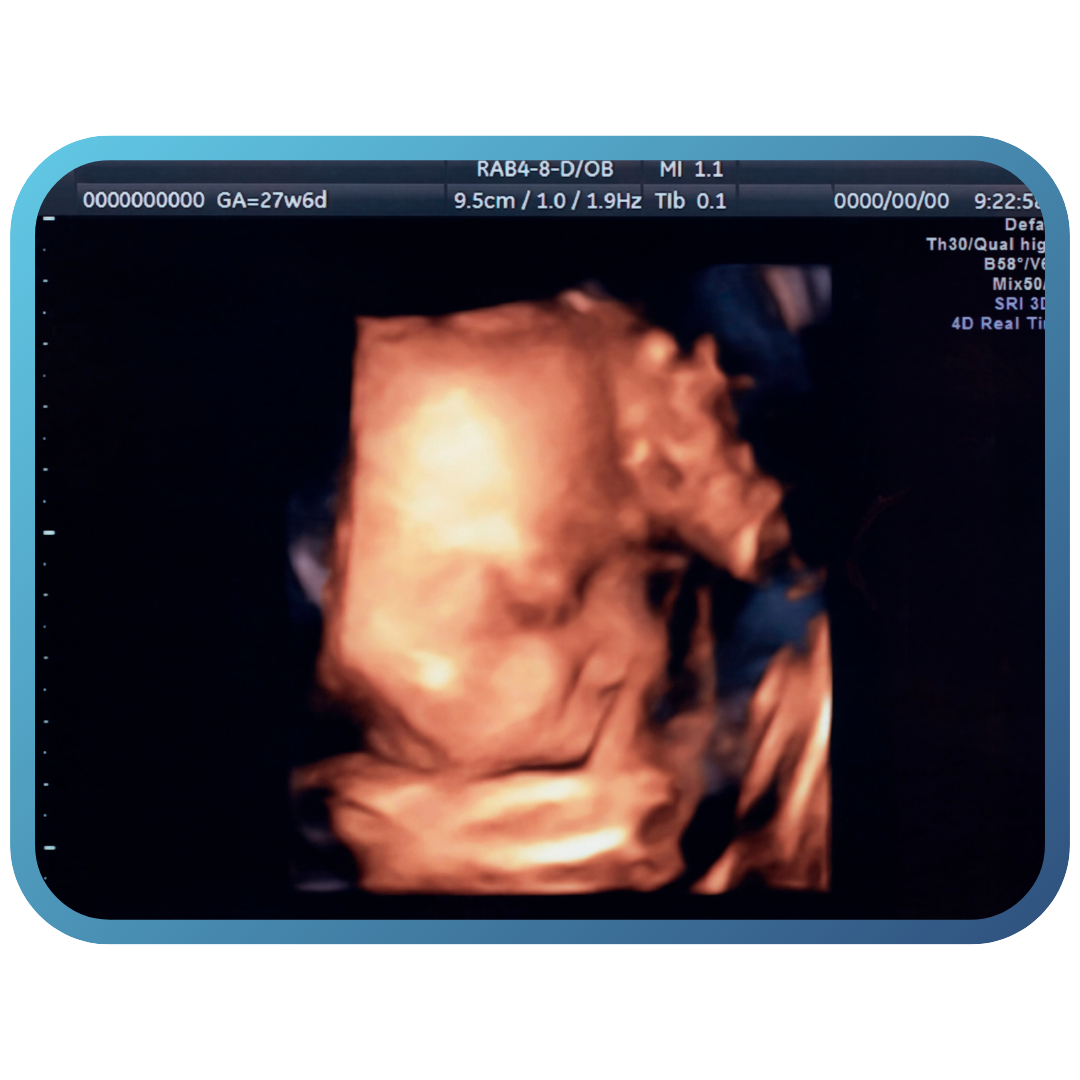

Exame avançado que permite ver o bebê em imagens 3D e em tempo real, com segurança, conforto e mais emoção para os pais.